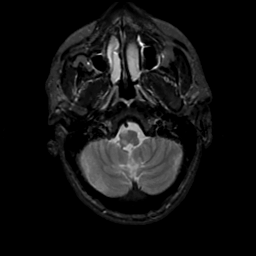

MR Study #16, June 23, 1991 -- Slice #7